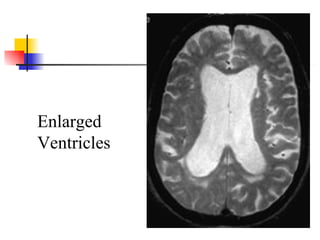

Diagnostic studies Ventricle enlargement on CT or MRI Severity graded by ratio of maximal frontal horn width divided by transverse inner diameter of skull 0.32 minimal for NPH but 0.40 more typical Lack of hippocampus or cortical atrophy Periventricular and cortical white matter lesions may be found in patients with NPH Large number white matter lesions may be marker for poor response to shunting

Enlarged Ventricles